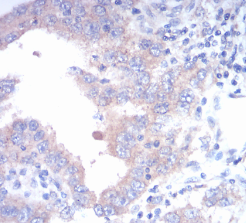

FGFR3 Mouse Monoclonal antibody[2H105]

Immunogen :   Purified recombinant fragment of human FGFR3 (AA: 529-694) expressed in E. Coli.

IHC    1/200 - 1/1000